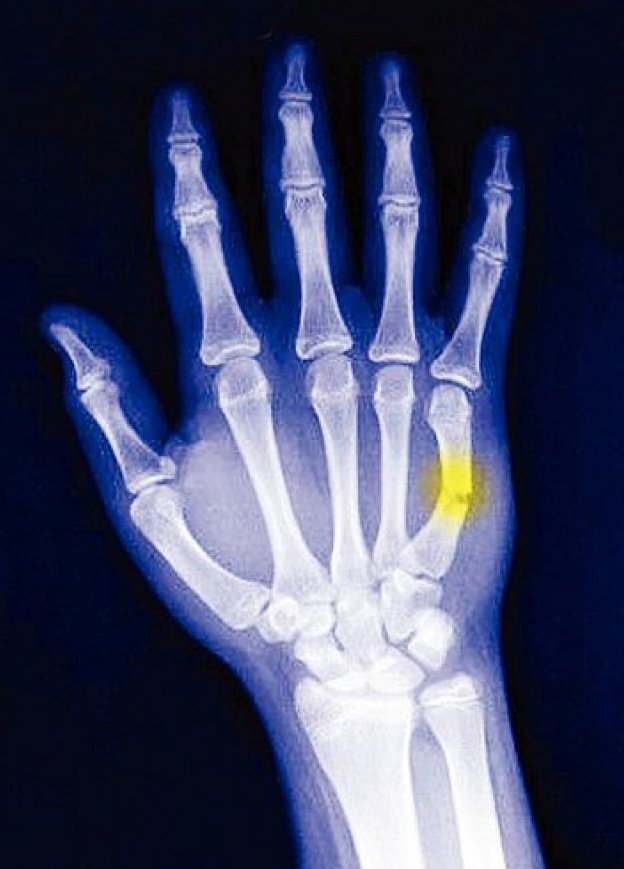

عادة ما يكون بالفحص السريري الذي يبين وجود الالآم حول المنطقة المصابة و صعوبة حركتها و ضمور العضلات المحيطة بها ، بعد ذلك يتم اجراء فحص الاشعة السينية واشعة الرنين المغناطيسي الذي يظهر فيها مكان الاصابة و شدته ومدى تأثر العظام